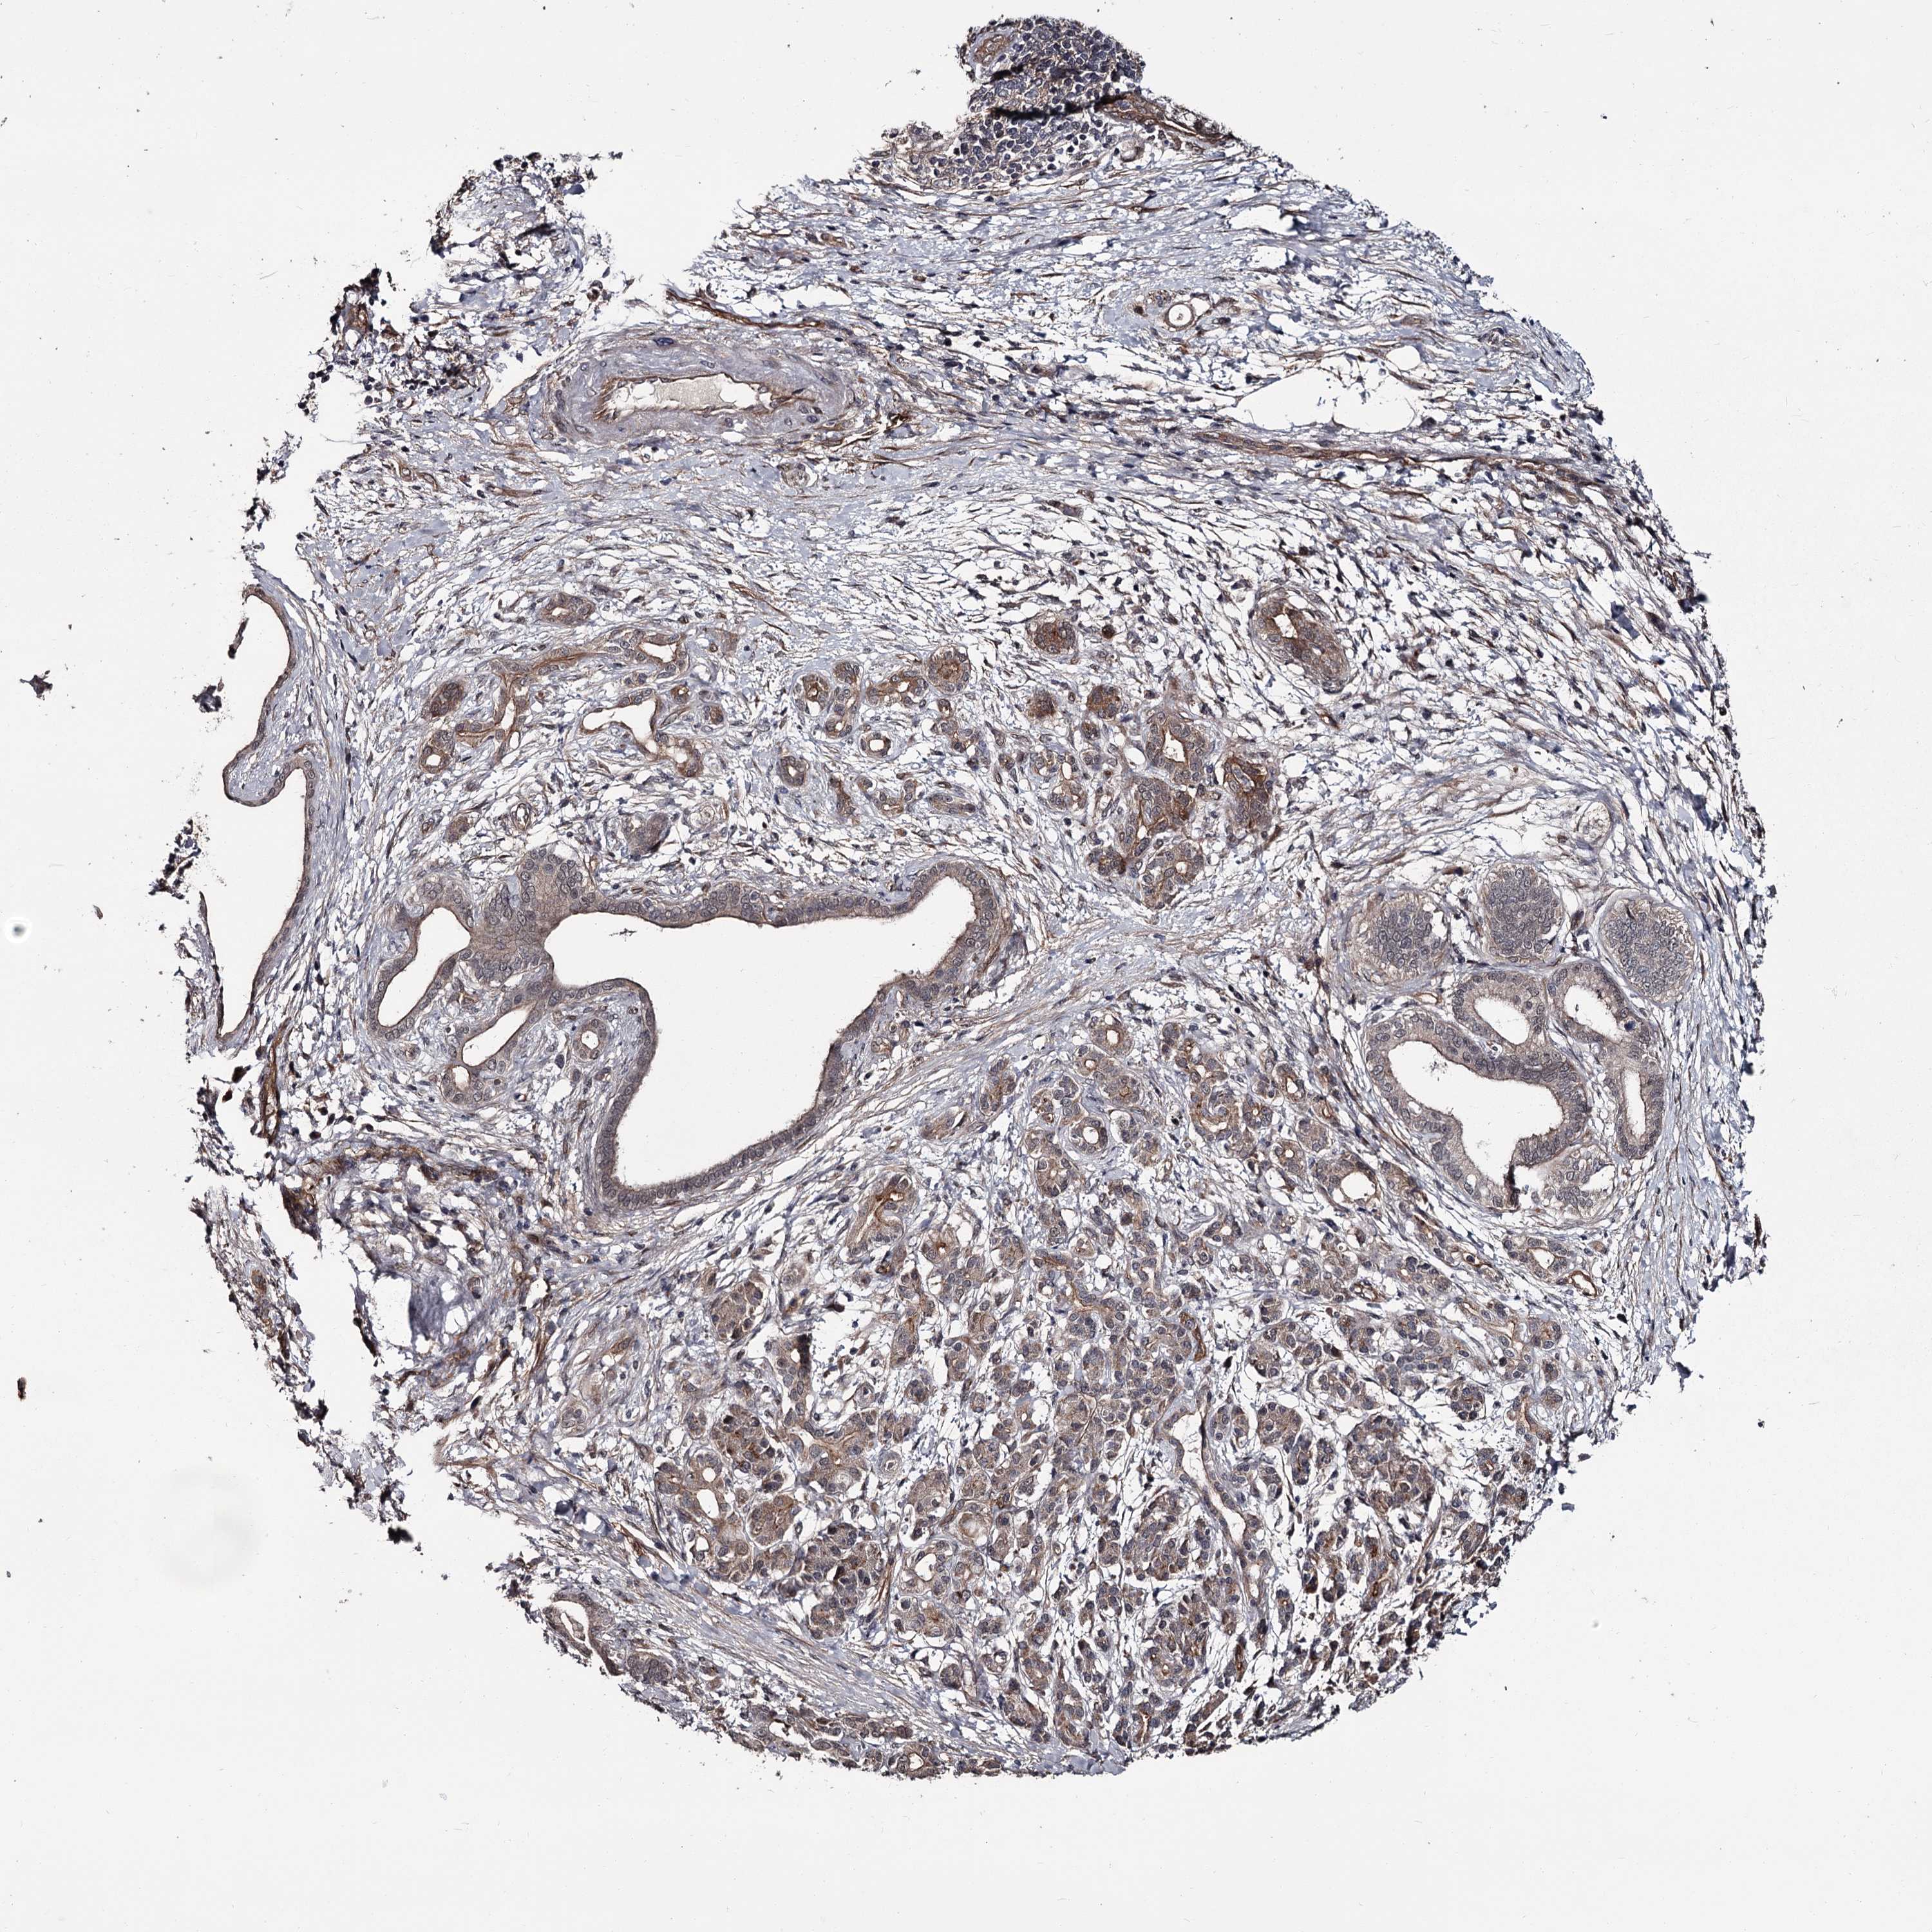

PANCREATIC CANCER - Protein expressioni

A mouse-over function shows sample information and annotation data. Click on an image to view it in a full screen mode. Samples can be filtered based on level of antibody staining by selecting one or several of the following categories: high, medium, low and not detected. The assay and annotation is described here.

Note that samples used for immunohistochemistry by the Human Protein Atlas do not correspond to samples in the TCGA dataset.

Antibody stainingi

Antibody staining in the annotated cell types in the current human tissue is reported as not detected, low, medium, or high, based on conventional immunohistochemistry profiling in selected tissues. This score is based on the combination of the staining intensity and fraction of stained cells.

Each image is clickable and will lead to virtual microscopy that enables deeper exploration of all samples and also displays staining intensity scores, fraction scores and subcellular localization as well as patient and tissue information for each sample.

Antibody HPA038562

Staining

High

Medium

Low

Not detected

Intensity

Strong

Moderate

Weak

Negative

Quantity

>75%

75%-25%

<25%

None

Location

Nuclear

Cytoplasmic/membranous

Cytoplasmic/membranous,nuclear

Adenocarcinoma, NOS